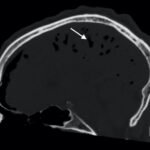

Tension pneumocephalus is a rare neurosurgical emergency requiring cranial decompression to prevent permanent neurological injury, herniation, and death. In this report, we present a trauma patient struck by a knife in the forehead who presented with agitation and vomiting. Imaging ultimately revealed a minimally displaced frontal sinus fracture through both the anterior and posterior walls of the sinus. This disruption, acting as a ball-valve for air entry into the cranium, resulted in extensive pneumocephalus and eventual tension physiology. The patient required immediate neurosurgical decompression. This case illustrates both the importance in recognition of this uncommon pathology as well as the need for rapid reassessment with clinical changes in trauma patients.